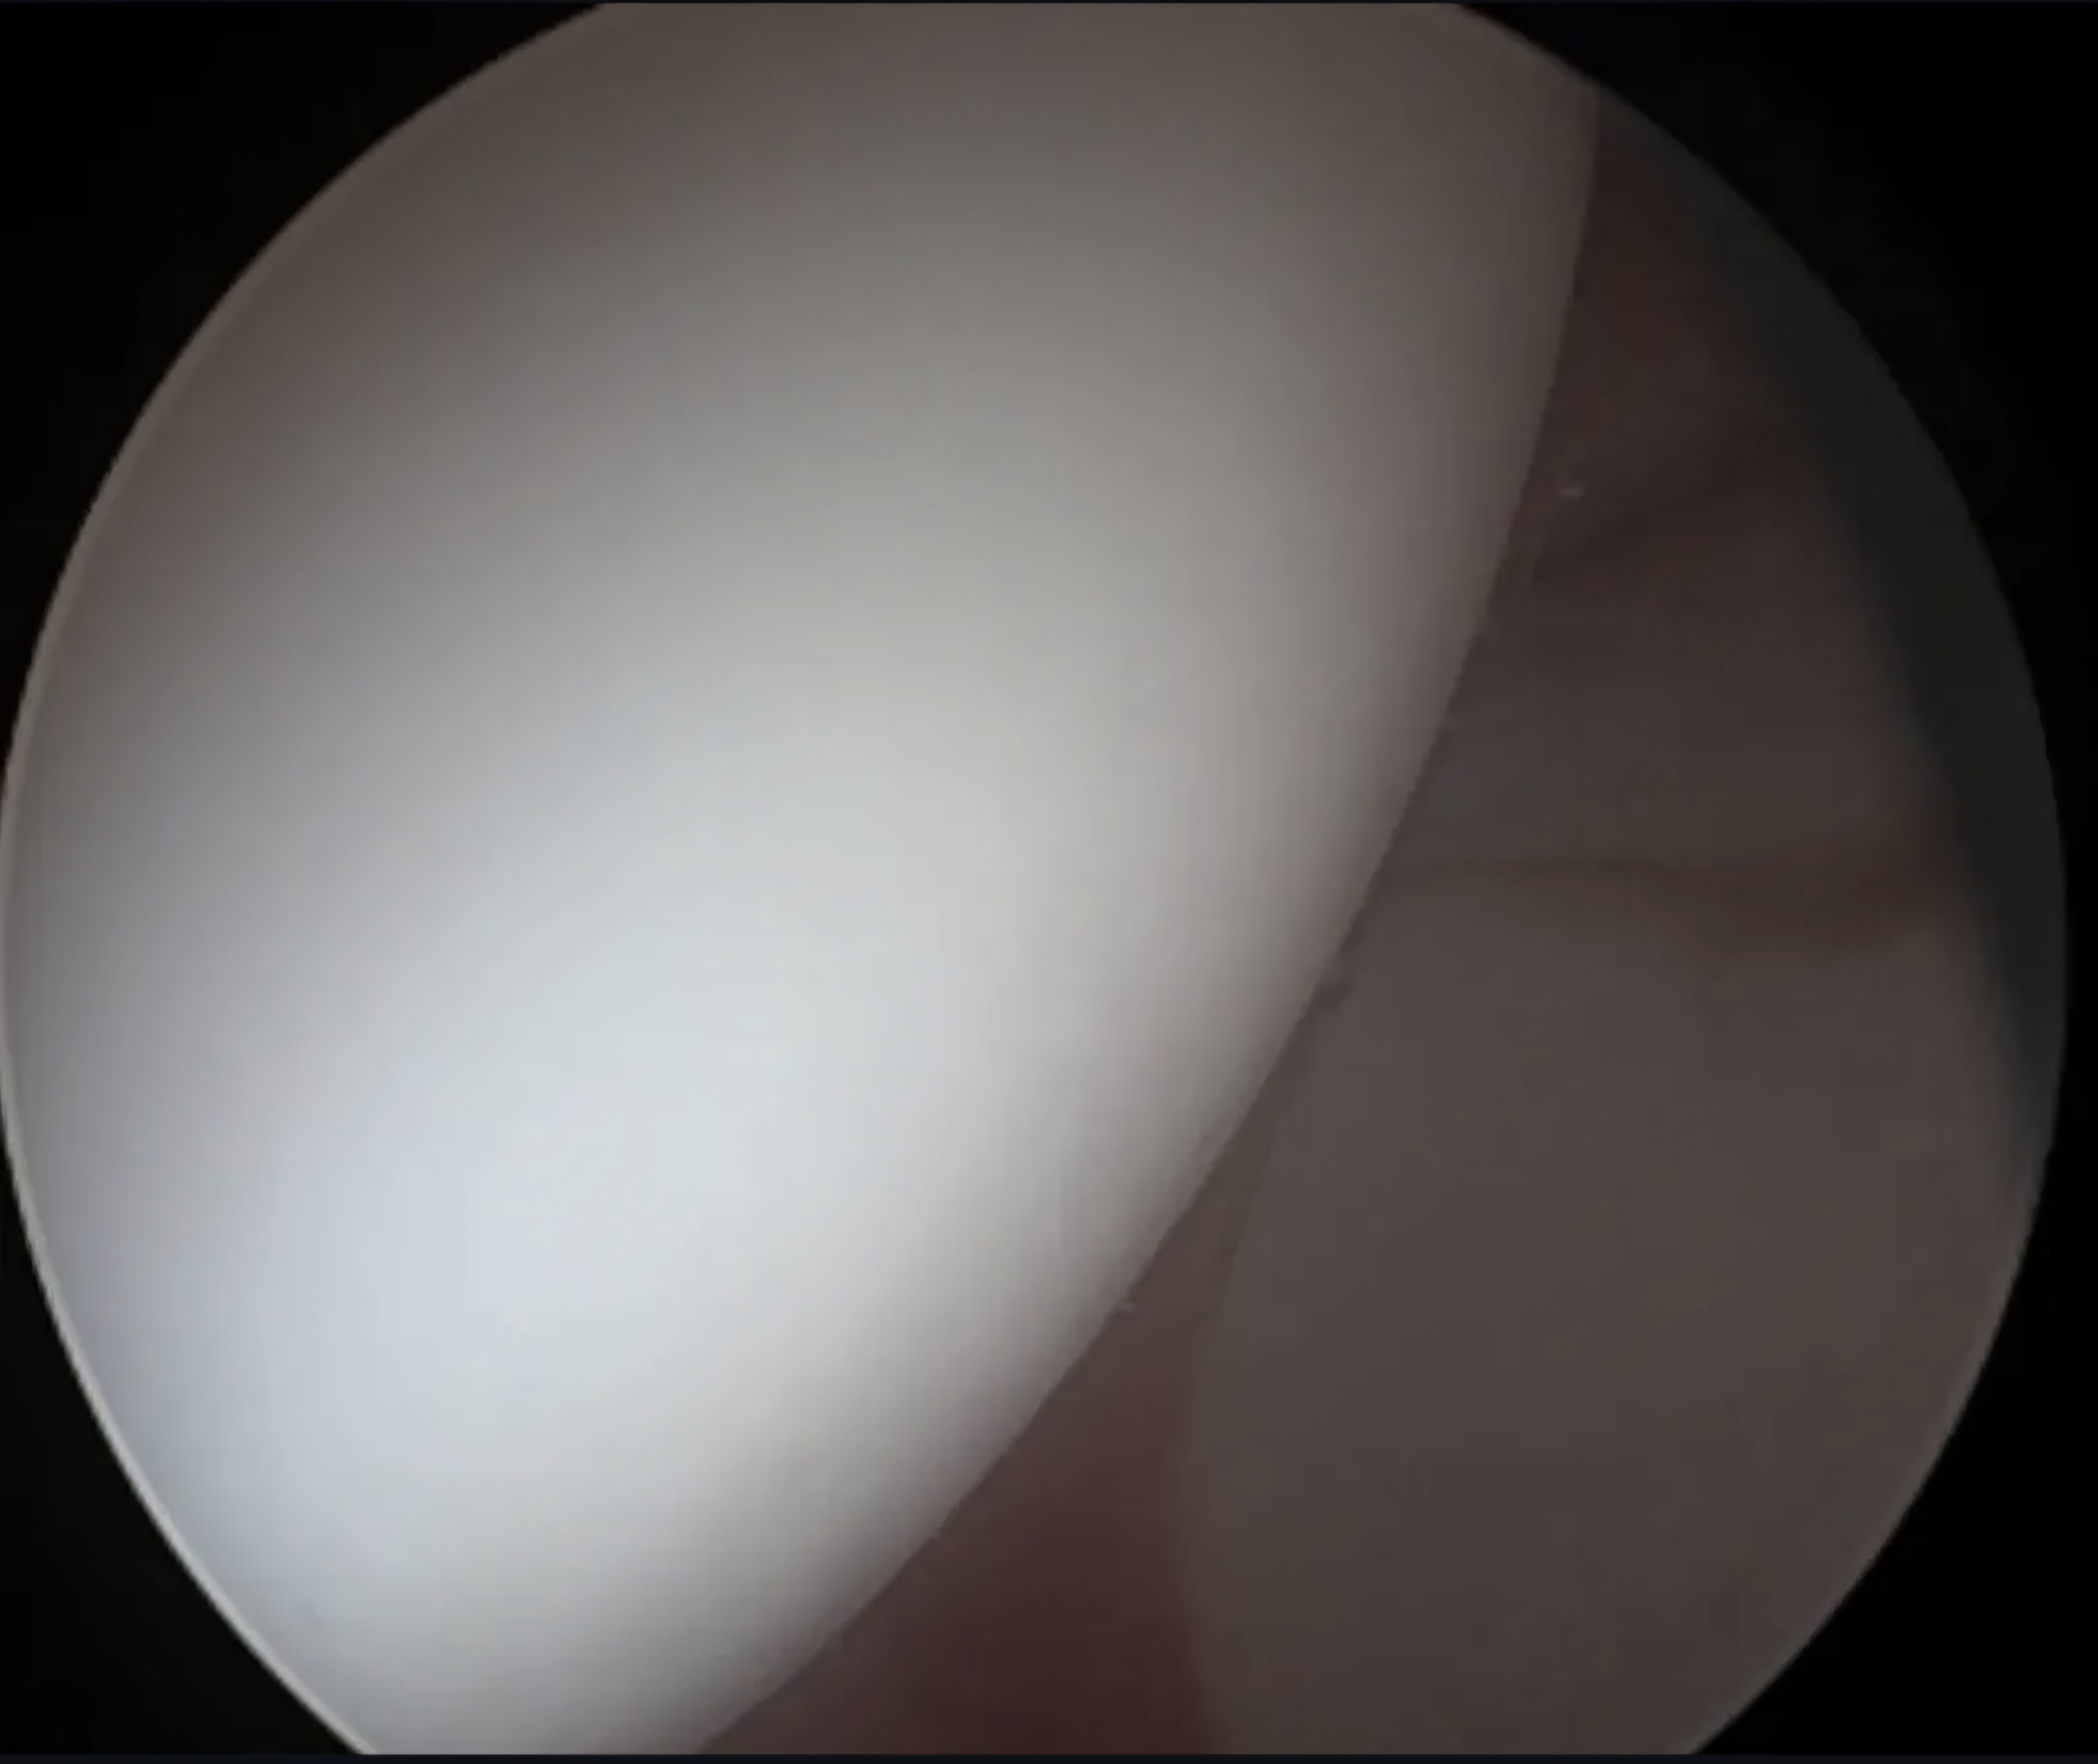

Η γωνία άλφα αποτελεί ένα ποσοτικό χαρακτηριστικό της μηροκοτυλιαίας πρόσκρουσης τύπου cam, σε περιπτώσεις ασθενών με χρόνιο πόνο στο ισχίο. Ωστόσο, τα όρια της γωνίας αυτής αποτελούν ακόμα ένα...